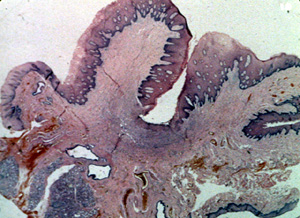

Esta

microfotografía de baja resolución

ilustra bien el aspecto lobulado de la lesión. Hay una

invaginación profunda en la porción central en que la pestaña de la

dentadura postiza fue localizada. |